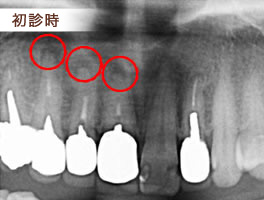

主訴 根尖病巣の治療

約1週間ごとに根管内の細菌に嫌気培養を行い無菌になるまで消毒を行う。

3~4回で無菌になったことを確認できるケースや3ヶ月から半年、またはそれ以上かかる症例もめずらしくありません。

治療内容 マイクロスコープを用いても拡大倍率が約20倍程度なので、根管の入り口が拡大されるだけで、根尖病巣の原因となっている細菌は実際に見ることが出来ません。

根尖病巣内の細菌を根管経由で採取して専用のチェアーサイド嫌気培養器で培養を行い 無菌になるまで消毒を繰り返します。

無菌になったことを確認して、根管内に根管充填剤を充填して治療を終了します。

根尖病巣の原因となっている細菌は、前回の根管治療の消毒で無菌にならず生き延びた強い細菌の集合体です。

通常の消毒薬ではなかなか無菌にならないので、それらの細菌に対して抗生物質感受性試験をおこない、最適な抗生剤を選び出して消毒に用いるケースも多々あります。